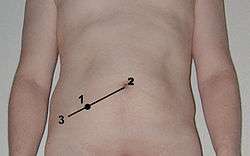

Location of McBurney's point (#1)

Location of McBurney's point (#1) The superior mesenteric artery and its branches